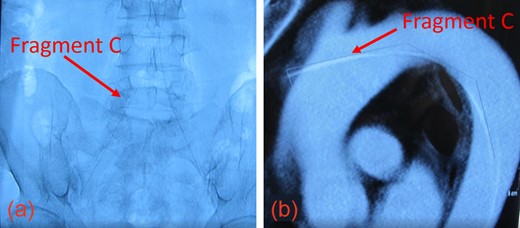

Intraoperative ultrasound confirmed the location of Fragment B in the right CCA (T1 vertebral level). We extended the CCA incision inferiorly to visualize the length of Fragment B, which was then removed intact using an artery clamp. Fig. 3a shows Fragments A and B, and Stent 1 after removal.

(a) Guidewire fragments and Stent 1 after removal from the patient. (b) CT image showing patent vasculature at 30 months post-operation.

The endarterectomy incision was repaired with polytetrafluoroethylene carotid patch, and intact vasculature was confirmed via fluoroscopy.

After a 1-week recovery in the intensive care unit, the patient returned to the operating room for removal of Fragment C, which was piercing the aortic arch. Via median thoracotomy, a purse-string suture was made around the point of penetration. A 6-Fr sheath was used to entrap thrombotic material as the guidewire was removed from femoral artery without incidence.

After surgery, the patient reported alleviation of his symptoms. Carotid vasculature remained patent with sufficient flow, and Stent 2 was still in place 30 months post-operatively (Fig. 3b). While the patient will require close follow-up, no complications have been reported to date, over 3 years after surgery. Informed consent was obtained from the patient prior to creation of this manuscript.